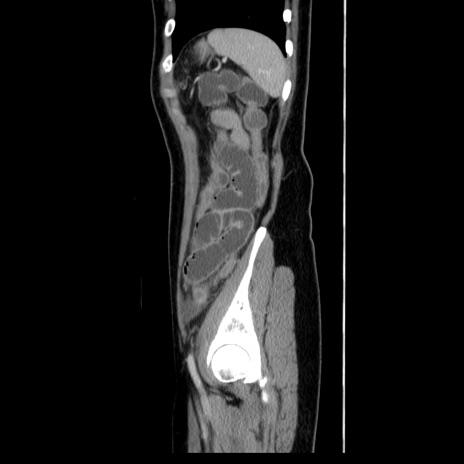

症例39(矢状断像)

【症例】40歳代女性

【主訴】上下腹部痛

【現病歴】2日目から下腹部痛あり。夜間は痛みで眠れなかった。昨日より上腹部痛と下痢が出現。臥位で痛みは軽快したため、休んでいた。本日になって臥位でも立位でも痛みが強くなってきたため救急要請。

【既往歴】子宮内膜症

【身体所見】部:平坦・軟、左上下腹部に圧痛あり、反跳痛あり。

【データ】WBC 21800、CRP 26.78

CT